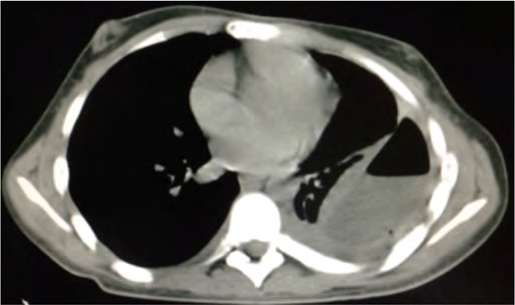

Um paciente do sexo masculino, jovem de 21 anos de idade, com diagnóstico prévio de esquizofrenia, foi internado para investigação de alteração na tomografia de tórax, conforme a imagem a seguir. A clínica apresentada era perda de peso, febre vespertina, tosse e um episódio de hemoptise. É familiar contactante de paciente com tuberculose ativa.

Acervo Pessoal.

Com base nesse caso clínico e nos conhecimentos médicos correlatos, julgue os itens a seguir.

Espera-se, na análise do líquido pleural desse paciente, um exsudato com predomínio linfocítico e ADA elevado.